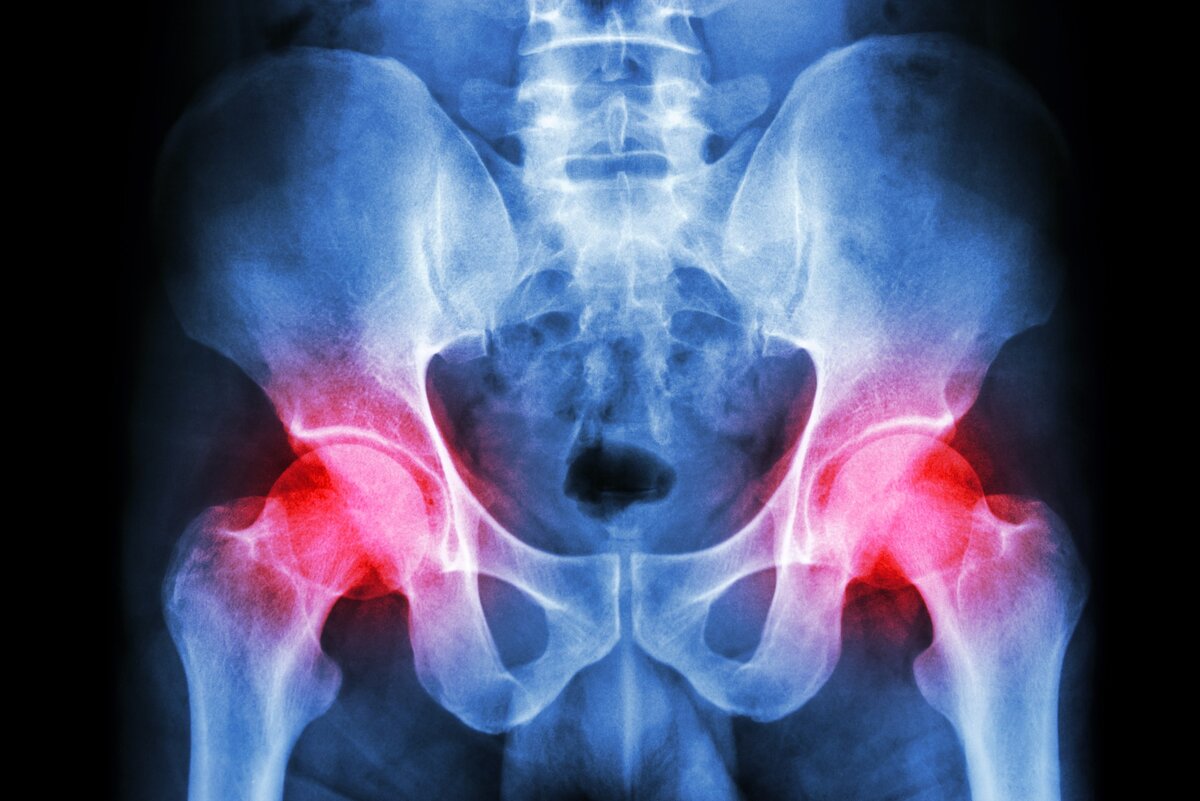

Коксартроз

В этой статье я расскажу вам о причинах коксартроза тазобедренных суставов и об эффективных методах лечения коксартроза и любых других суставов без операции. Наш организм очень рационален и не допускает бесполезного использования своих ресурсов. Поэтому все, что не используется или используется в минимальной степени, снабжается ресурсами по остаточному принципу, или, проще говоря, – атрофируется. Например, длительно неиспользуемая мышца становится тонкой и слабой, или при длительном ношении гипсовой повязки фиксированные без движения суставы теряют подвижность. Наше тело думает – хозяин не пользуется этим, значит, это не нужно, значит, можно забыть про эту область, не восстанавливать и не поддерживать ее в рабочем состоянии. Эта участь часто постигает тазобедренные суставы - у человека появляется боль, разрушаются хрящи, теряется подвижность и т.д. Почему так происходит? Потому что тазобедренные суставы рассчитаны на большой объем движений и тяжелую нагрузку, а в обычной жизни вся наг

В этой статье я расскажу вам о причинах коксартроза тазобедренных суставов и об эффективных методах лечения коксартроза и любых других суставов без операции.

Наш организм очень рационален и не допускает бесполезного использования своих ресурсов. Поэтому все, что не используется или используется в минимальной степени, снабжается ресурсами по остаточному принципу, или, проще говоря, – атрофируется. Например, длительно неиспользуемая мышца становится тонкой и слабой, или при длительном ношении гипсовой повязки фиксированные без движения суставы теряют подвижность. Наше тело думает – хозяин не пользуется этим, значит, это не нужно, значит, можно забыть про эту область, не восстанавливать и не поддерживать ее в рабочем состоянии. Эта участь часто постигает тазобедренные суставы - у человека появляется боль, разрушаются хрящи, теряется подвижность и т.д.

Почему так происходит? Потому что тазобедренные суставы рассчитаны на большой объем движений и тяжелую нагрузку, а в обычной жизни вся нагрузка ограничивается неспешной ходьбой до ближайшего магазина и подъемом на лифте даже на 2й - 3й этаж.